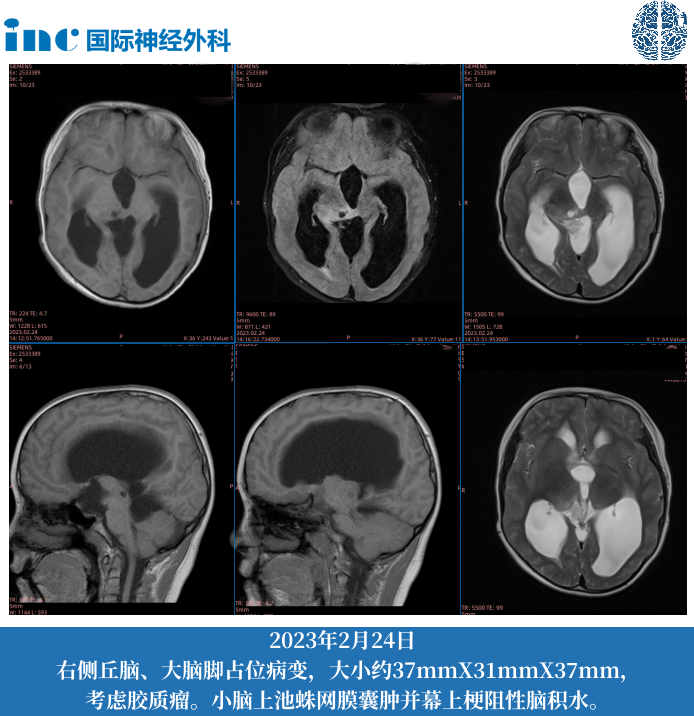

2023年年初,诺诺的行动能力、平衡能力明显下降,学校老师也告知家长诺诺在学校期间的行动能力状况。2月24日去当地儿童医院神经内科检查发现脑积水、颅内占位,转神经外科住院手术,脑脊液造瘘手术。3月13日出院,开始中医治疗,期间就诊某医院服用“平消胶囊”3月有余,至今状态尚佳。5月去北京某医院,医生诊断“顶盖胶质瘤”。